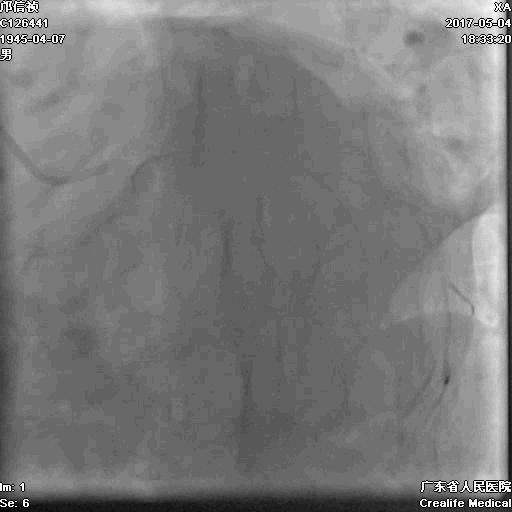

逆向通道:1. LCX---PL?

2.LAD---PDA?

正向浅尝,改为逆向,LCX-PL

RRA:6F AL0.75 GC –RCA;

RFA:7F XB 3.5 GC—LCA 150cmcorsair